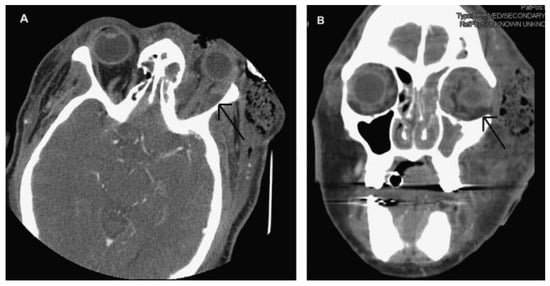

The patient was taken immediately to the operating room due to her worsening clinical presentation and the authors’ suspicion for necrotizing soft tissue infection. Incision and drainage and debridement of the necrotic tissue were performed on the left periorbital, zygomatic, and temporal regions (►Figure 3A–D). Copious purulent drainage was obtained which was submitted for Gram stain and cultures. Irrigation of the wound was then performed until no further murky fluid was appreciated with approximately 5 L of 0.9% normal saline. The wound was then packed in a standard wetto-dry fashion. The patient was placed on vancomycin, piper-acillin/tazobactam, and metronidazole and transferred to the intensive care unit (ICU) where she remained intubated and sedated. In the ICU, she was supported medically, including optimization of her blood glucose. Overnight, the patient remained tachycardic and febrile with a maximum temperature of 103°F (39.4 °C). At that time, a maxillofacial CT with contrast was obtained, which revealed left periorbital, orbital, and buccal inflammatory changes. Proptosis, lateral and downward displacement of the globe, and homogeneous opacification of the frontal, ethmoid, and maxillary sinuses were appreciated on the left side. The right ethmoid sinus was partially opacified, which justified the inflammatory changes in the right orbit. Additionally, a large fluid loculation of the left lateral pharyngeal space was present (►Figure 4). The intraoral examination revealed a large localized swelling of the left oropharynx and nasopharynx, with deviation of the palatal uvula from the midline. Ophthalmology was reconsulted. On postoperative day 2, the patient was taken back to the operating room for incision and drainage of the left maxillary sinus and left lateral pharyngeal space and washout of existing wound. An intraoral incision was made on the left posterior oropharynx and blunt dissection was performed to enter the left lateral pharyngeal space where approximately 15 mL of purulence was obtained and samples were sent for cultures and sensitivities. Three nonrestorable, grossly carious left maxillary posterior teeth were then extracted to negate any possible source of odontogenic infection; however, no purulence or periapical involvement of the teeth was evident upon extraction. This made an odontogenic cause of the infection unlikely. The left maxillary sinus was entered via a standard Caldwell-Luc approach to drain the fluid collection appreciated on CT and an additional 5 to 10 mL of purulence was obtained. After copious irrigation of the sites, two ½ inch Penrose drains were placed, one in the left maxillary sinus and the other in the left lateral pharyngeal space. The drains were then secured to the oral mucosa with sutures. Washout and redressing of the left periorbital wound was then performed and the patient returned to the ICU intubated. Laboratory values showed white blood cell count of 15.9 g/dL, hemoglobin of 12 g/dL, hematocrit of 36.4%, and platelet count of 226,000/µL. Chemistry showed sodium level of 134 mmol/L, potassium level of 3.5 mmol/L, chloride level of 97 mmol/L, bicarbonate level of 27 mmol/L, blood urea nitrogen level of 6 mg/dL, creatinine level of 0.7 mg/dL, and glucose level of 375 mg/dL. Hemoglobin A1C was 12.8 and C-reactive protein was 34.2 mg/dL. The patient’s previously recorded hemoglobin A1C was 13.0 recorded 26 months earlier at the medicine clinic showing long-term poor diabetic control. Over the next few days, the patient clinically improved and her vital signs stabilized with the exception of a persistent elevated temperature of 101°F. Cultures came back as group C β hemolytic Steptococcus and Proteus mirabilis. After consultation with the infectious disease service, the antibiotics were narrowed to ampicillin/sulbactam and clindamycin. A repeat CT scan was obtained on hospital day 5 and a loculation was noted at the superior and lateral aspect of the left orbit, suggestive of subperiosteal abscess (►Figure 5A,B). Ophthalmology service recommended no intervention for the left orbital subperiosteal abscess. However, as the patient was still having low-grade temperature of 101°F (38.3 °C), the authors took the patient back to the operating room for incision and drainage of this area. We approached the superior-lateral orbit via an existing incision, and approximately 5 mL of purulence was obtained. Postoperatively, the patient improved clinically, and became afebrile. The intraoral drains were removed, and after cons ultation with the wound nurse, the wet-to-dry dressing of the skin was changed to petroleum-impregnated gauze. Despite our objection, the patient remained intubated for a prolonged period due to the discomfort of the ICU team in extubating the patient. The patient was extubated on hospital day 12. On the day of discharge, examination revealed significant decrease in left periorbital swelling, decrease proptosis, and increase extraocular movement in all directions; however, she continued to have 20/400 vision in the left eye and diplopia. Due to the defect in the left upper and lower eyelids, a home care nurse was assigned for daily dressing changes. Intraoral examination demonstrated resolution of swelling of the oropharynx. A maxillofacial CT scan revealed resolution of the original fluid loculations and a patent airway. Throughout the postoperative hospital stay, the patient’s glucose level and blood pressure were controlled. The patient was discharged on hospital day 13 with oral antibiotics, amoxicillin/clavulanic acid, and clindamycin, as well as her home antihypertensive and diabetic medications. The patient was closely followed up and her condition continued to improve. At 4 months follow-up, the patient presented with resolution of facial swelling; had proptosis and eyelid ptosis, normal extraocular movements; and her baseline visual acuity of her left eye remained 20/400. The patient was seen 1 year postoperatively and had continued resolution of her wounds with appropriate wound closure; however, she had continued strabismus, ptosis of the upper and lower lid secondary to scar contraction, as well as left V2 paresthesia (►Figure 6A,B). The orbital wound continued to heal via secondary intention with anticipated reconstruction and scar revision in the near future.

Figure 5. Axial and coronal computed tomographic scan illustrating a sub-periosteal abscess at the lateral (A) and superior (B) aspect of the left orbit. Arrow on A shows abscess on lateral orbit and arrow on B shows abscess on inferolateral orbit.